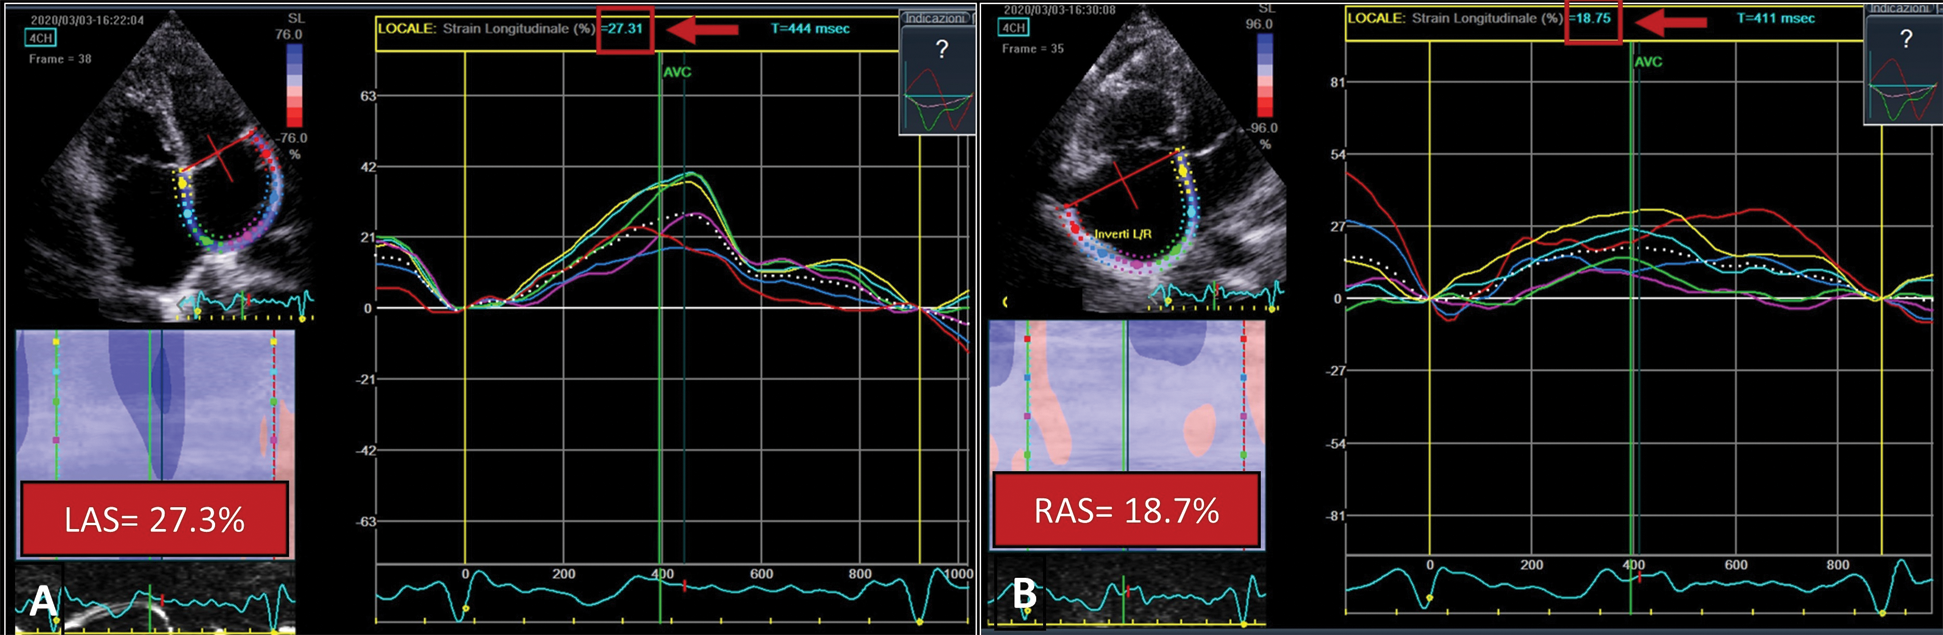

However, left and right atrial strain were below the reference ranges (Left Atrial Strain 27.3%; Right Atrial Strain 18.7%) [1,2] (Fig. 2).

Figure 2: Atrial strain. Measurement of left atrial (Panel A) and right atrial (Panel B) longitudinal strain by speckle tracking. The atrial endocardial border is traced, divided in 6 regions and then analyzed by a semi-automatic software. After approval, segmental longitudinal strain curves are generated (solid-colored lines). The dashed line represents the average strain. Both indexes are below reference ranges. LAS = Left Atrial Strain; RAS = Right Atrial Strain